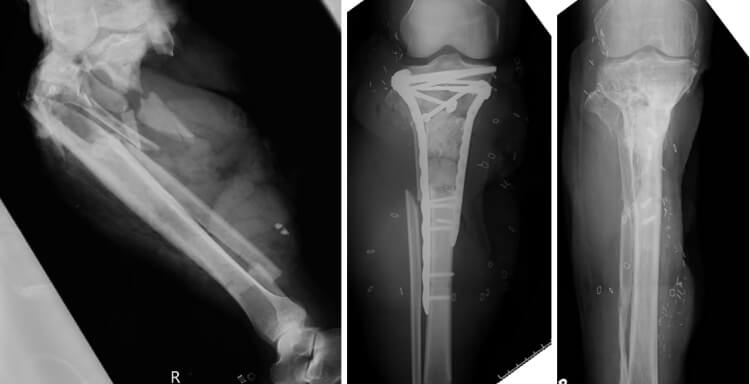

四肢開放骨折症例

転落外傷による脛骨重度開放骨折の症例。骨接合術および形成外科による遊離皮弁術など複数回手術を経て、最終的には疼痛なく独歩可能となりました。